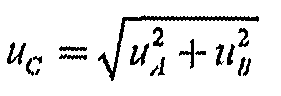

6.5. Рассчитывают суммарную стандартную неопределенность, %, по формуле:

(9)

6.6. Вычисляют расширенную неопределенность, %, для доверительной вероятности Р = 0,95 по формуле:

(10)